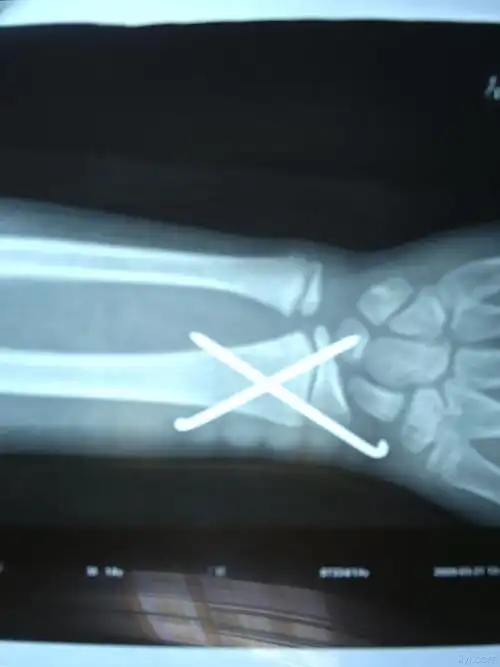

桡骨远段骨骺分离一例